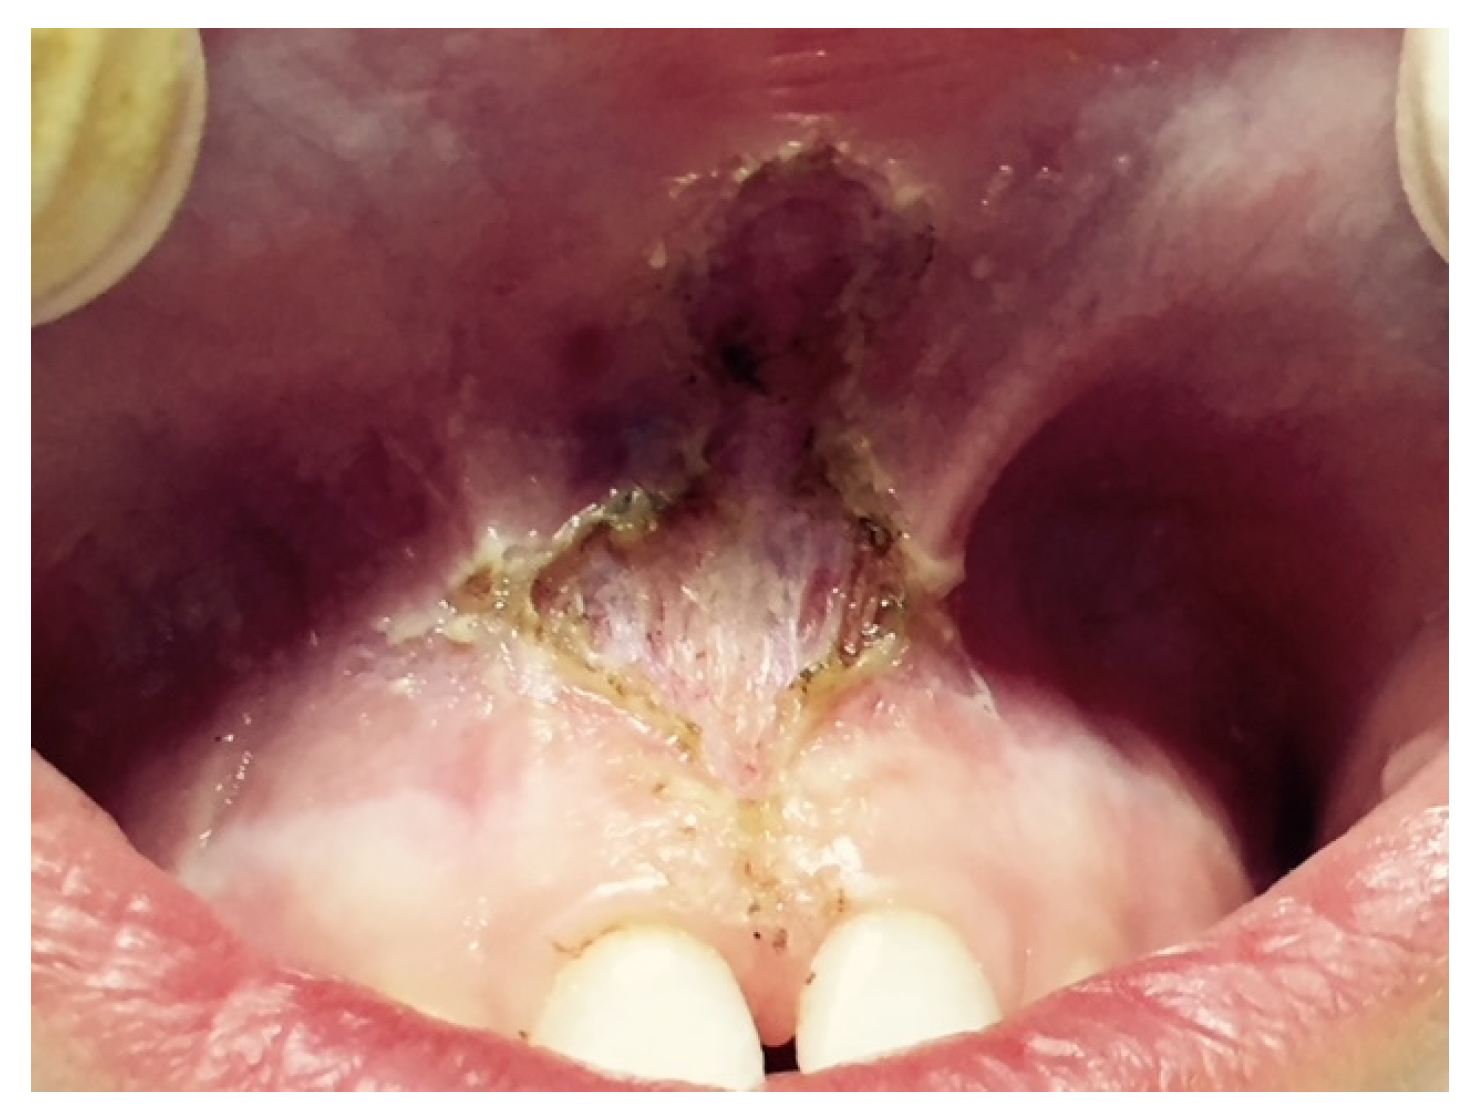

Furthermore, the diode laser has become highly popular in dental practice given its small size, low cost and easy application for minor soft tissue surgery, for its properties of straightforward tissue incision, and its coagulation and post-surgery benefits [26,27] (Figure 7).

Figure 7.

Labial frenulum treated by laser frenectomy after healing.